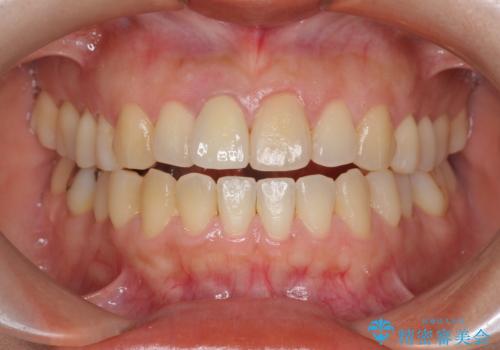

オーダーメイドで造る、自然な前歯セラミッククラウン

- 幼少期に前歯をぶつけて歯が折れ、神経の治療・クラウン治療を行った。グラつきと見た目の改善を希望して来院されました。

精密な仮歯をいれ、歯周組織を整えるとともにファイバーコア築盛、シェードテイキングを行い見た目に自然なジルコニアクラウンを製作していきます。

ジルコニアクラウンの中でも当法人のグレードの高い、スペシャル・エクセレントプランはオーダーメイドで色調を合わせることで周囲の歯に馴染んだ自然な歯を製作することのできるプランです。